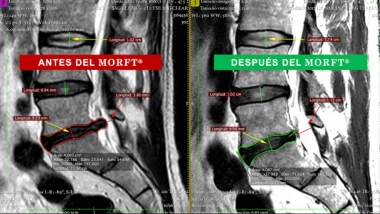

Sin medicamentos ni cirugías, el método MORFT® rehabilita a pacientes que viven con protusión y/o hernia discal